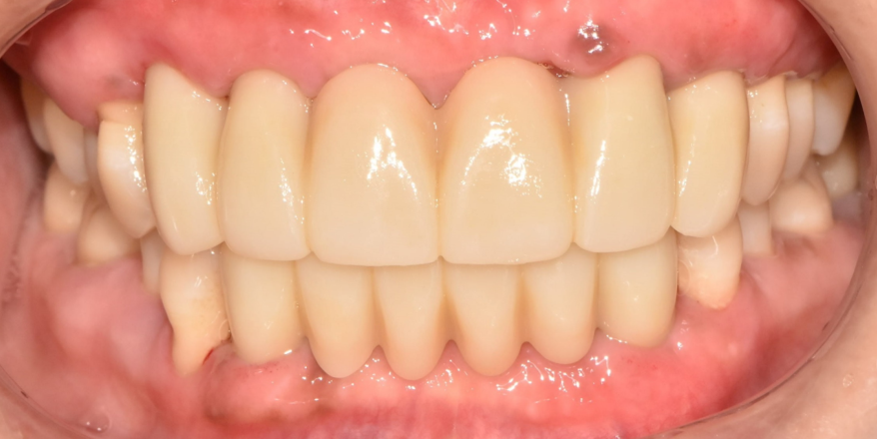

자 이제 크라운까지 씌우면 모든 과정이 마무리되겠군요.

전후 사진을 보고 깜짝 놀라시면 안됩니다ㅎㅎ 동일인이 맞나 여러 번 확인하게 되실 겁니다.

낙성대역 치과 에서는 본래 갖고 있던 치아의 색조와 형태를 재현하여 크라운 제작을 마쳤습니다.

어떤가요? 심미면에서도 위화감 없이 주변 조직과 조화롭게 잘 이루어지며 단단하게 심어져 자연치의 기능을 회복할 수 있겠네요.

일상생활 곳곳에서 불편함을 느끼셨을 환자분,

이제 맛있는 음식을 편하게 드실 일만 남으셨네요!

부디 청결한 관리와 정기검진으로 오래오래 유지하기 바랍니다^^